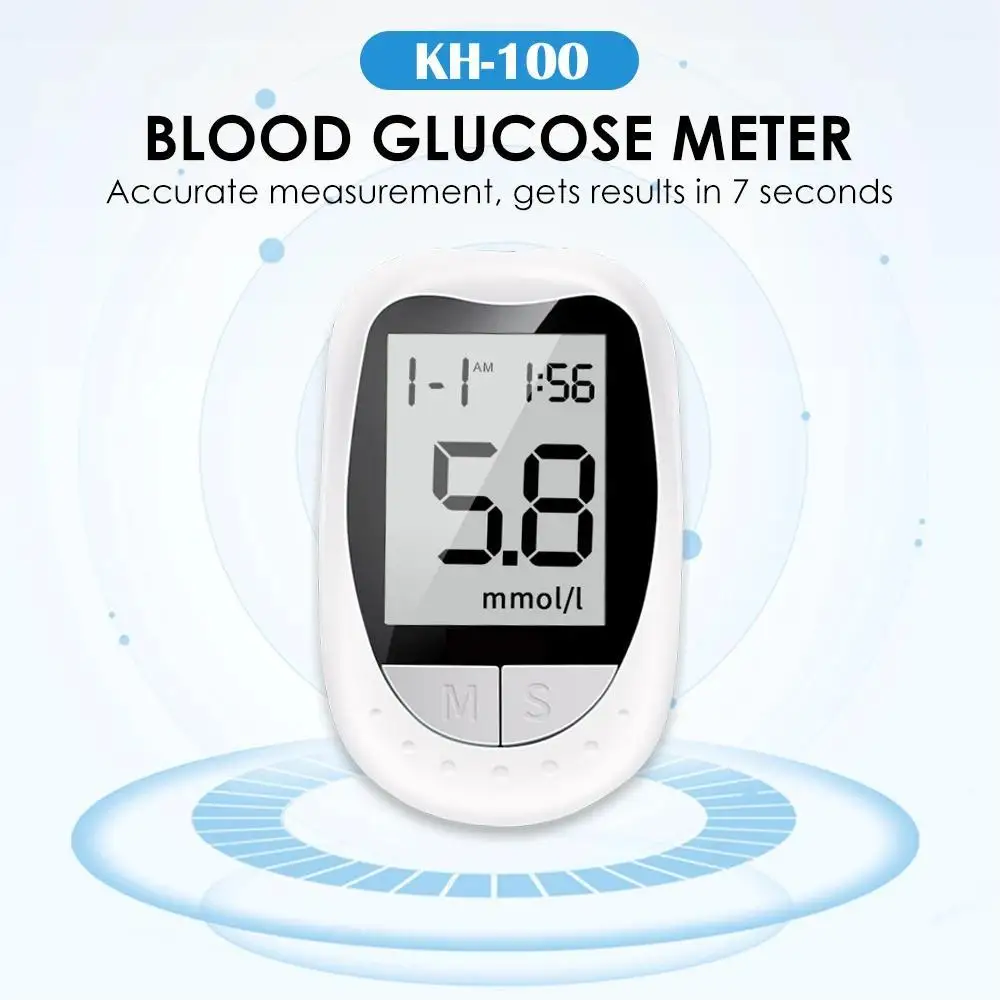

Application: Fingers

Power supply: CR2032 button battery (not included)

Units: mmol/L and mg/dl

Test range: 1.1-33.3 mmol/L (20-600mg/dl)

Test sample: whole blood of capillaries

Minimum volume added: 1ul

Test time: 7s

Battery life: tested approximately 1000 times

Memory value: 200x

HCT range: 30-55%